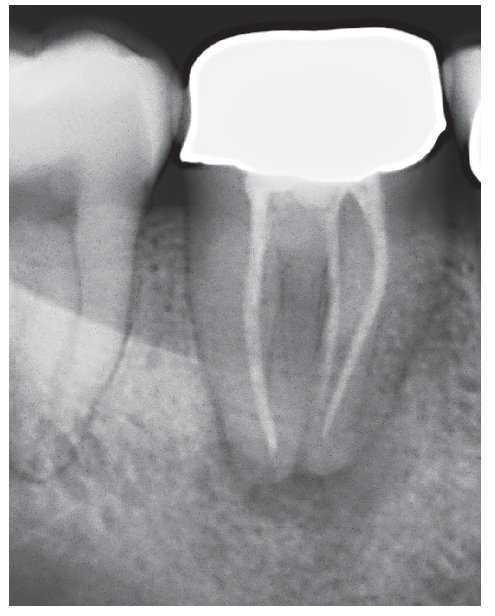

Figura 1a. Radiografía diagnóstica ortorradial del diente 43: una imagen radioopaca «interrumpe» el conducto radicular en el tercio medio de la raíz, fuerte curvatura apical del conducto radicular hacia mesial.

Figura 1b. En el segmento coronal de la raíz se observan dos conductos radiculares orientados en sentido vestibulolingual que están unidos por un istmo.

Figura 1c. En la proyección excéntrica de la conductometría se aprecia claramente la configuración tipo VI de Vertucci: los dos conductos radiculares están separados por un septo en el tercio medio y se unen nuevamente por debajo de éste mediante un istmo en el que se encuentran todavía restos de CaOH de la primera sesión. Los dos conductos muestran una trayectoria divergente en sentido apical para acabar en un foramen apical cada uno.

Figura 1d. Situación clínica en el momento de la adaptación del cono maestro para la compactación vertical en caliente.

Figura 1e. Radiografía de control después de la obturación termoplástica. Se logró una obturación homogénea y completa de este sistema de conductos radiculares complejo.